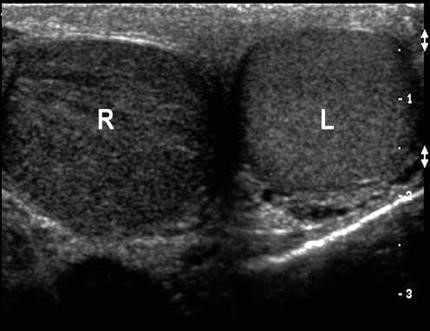

6. Then move to the “buddy view,” which is a transverse view of both testicles in the same image. Compare both testicles echogenicity, blood flow, and size. In a testicular torsion, you should see a decrease in echogenicity on the affected side (Figure 1), while in epididymitis you will generally see normal echogenicity and enlargement of the epididymis (Figure 2). Of note, echogenicity may be normal in intermittent or early torsion cases.

Figure 1. Left testicle normal with right testicular torsion and hypoechogenicity. Courtesy of Michael Blaivas, MD